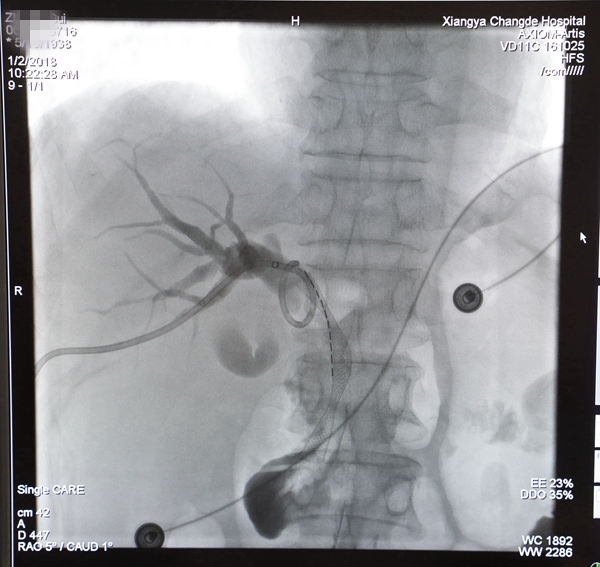

1月2日,在放射介入中心主任胡康新教授的指导下,汤金成和李毅副主任医师为患者实施了手术。手术在DSA机引导下进行,首先行经皮穿刺肝胆管造影术,医师手法熟练、精确判断,很快便找到肝胆管梗阻部位,并对梗阻胆管进行了疏通并安放了一个支架,解除了患者的胆道梗阻并建立了内引流通道;随后在支架内胆管癌部位植入碘125放射性粒子,对肿瘤进行近距离放射治疗;最后,还放置了一个胆道外引流管进行外引流。手术在局麻下进行,全程仅一个小时,术中患者几乎无痛苦,完全达到手术预期目的,术后患者及其家属均表示十分满意。

术后胆道支架及碘125放射性粒子影像